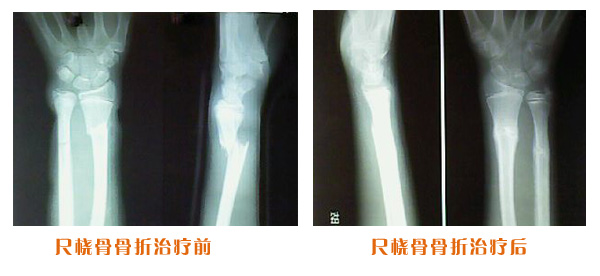

肥城市安駕莊梁氏骨科醫院是一所以梁氏手法正骨配合膏藥為特色的現代化??漆t院。

梁氏骨科術始創于清雍正年間,歷經八代,至今已有三百年歷史。據1929年泰安縣志載“梁瑞圖先生,字增生,號蓮峰,安駕莊人,精岐黃并發(fā)明接骨,凡跌打車凡跌打車軋皮不破而碎骨者......【詳細】 |